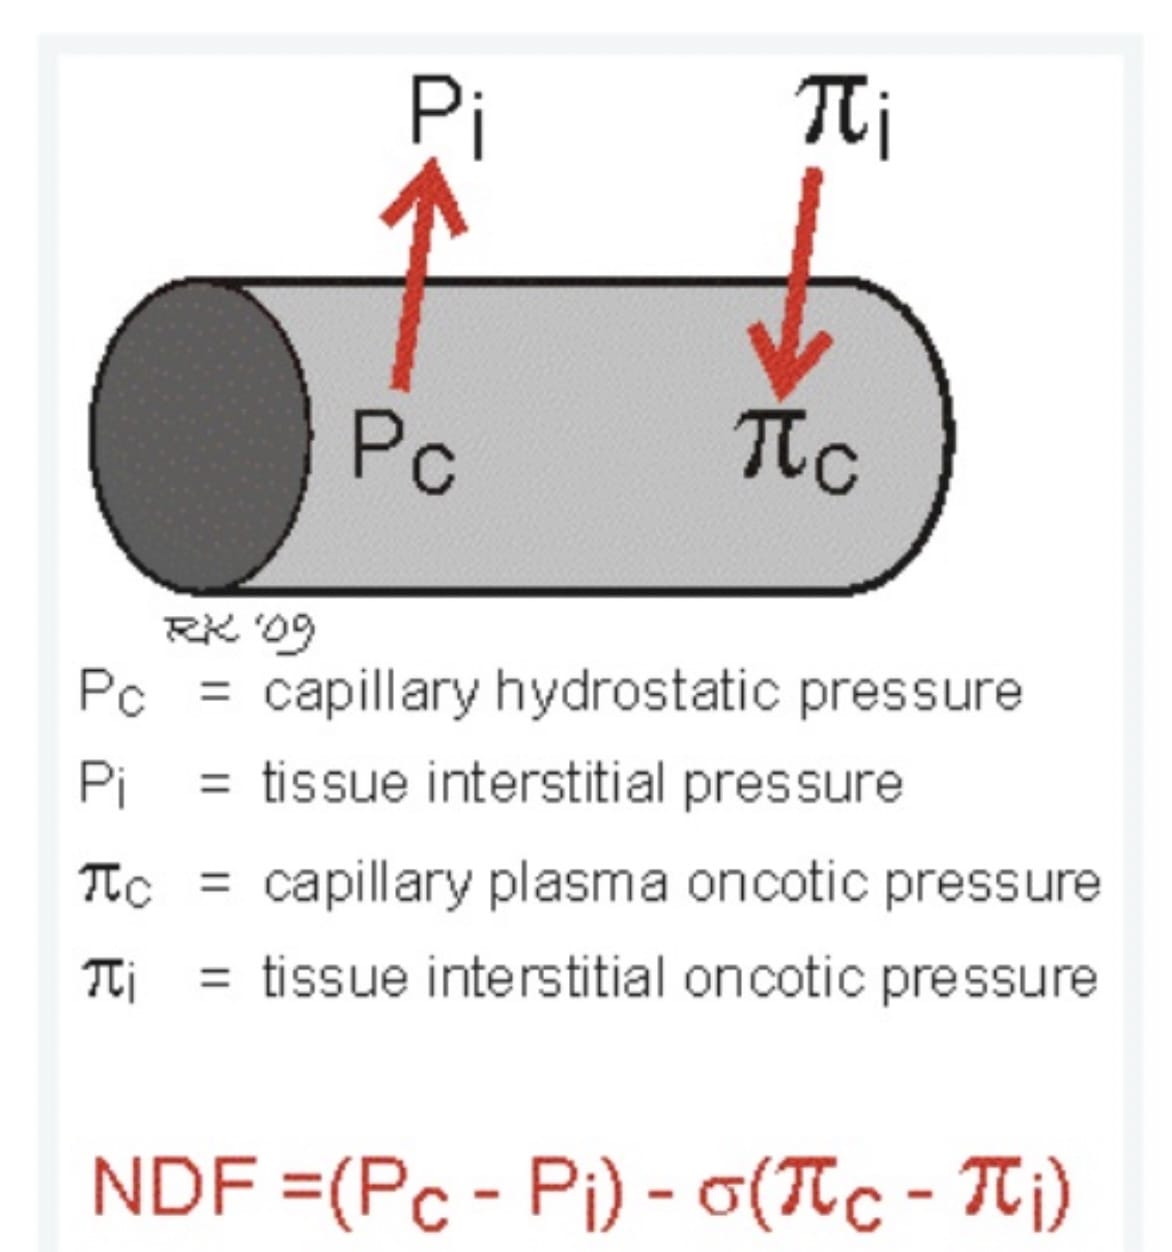

The Starling Equation describes the factors determining fluid filtration across the pulmonary capillary.

NDF represents the net driving force for fluid filtration

σ represents a reflection coefficient for movement of large molecules (such as protein) across the capillary wall - from 0 if completely permeable to 1 if impermeable.

The Starling Equation in the Lung

Source: https://www.anaesthesiamcq.com/FluidBook/fl4_4.php